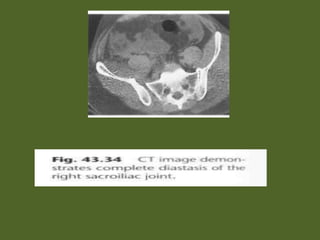

• Fig. 43.32 Traumatic avulsion of the right

diastasis of the right sacroiliac joint has occurred.

• Fig. 43.32Traumatic avulsion of the right superior gluteal artery (arrow) from pelvic trauma. Bleeding from branches of the internal iliac artery is also seen (open arrows). Marked diastasis of the right sacroiliac joint has occurred.